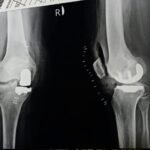

Partial Knee Replacement Surgery

Partial knee replacement is a surgical procedure in which only the damaged portion of the knee joint is replaced, while the healthy parts of the knee are preserved. Unlike total knee replacement, this surgery focuses on the specific area of the knee affected by arthritis, most commonly the inner (medial) compartment.

Yes. If arthritis progresses to other parts of the knee over time, partial knee replacement can be revised to total knee replacement if required.